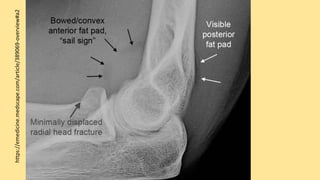

https://emedicine.medscape.com/article/389069-overview#a2

These bones giverise to 02 joints: HUMEROULNAR JOINT is the joint between the pulley like trochlea on the medial aspect of the distal of the humerus and the trochlear notch on the ulna. Humeroradial joint is the joint between the capitulum on the lateral aspect of the distal end of the humerus with the head of the radius. The humeroulnar and the humeroradial joints are the joints that give the elbow its characteristic hinge like